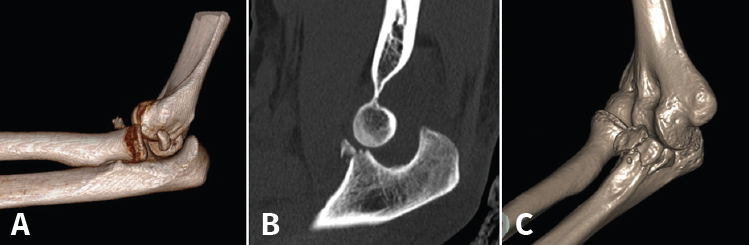

Fractura de Monteggia y lesiones Monteggia-like

Son lesiones poco frecuentes pero complejas. Es esencial una reconstrucción anatómica precisa del cúbito proximal para recuperar la funcionalidad del codo. La restauración anatómica de la longitud y las dimensiones del cúbito será crucial para la congruencia de la articulación radiocapitelar. Una reconstrucción fallida o inadecuada acabará con dolor persistente y una progresiva degeneración de la articulación. Hay que poner especial atención en 2 fragmentos: la faceta anteromedial de la coronoides y la faceta anterolateral del cúbito, junto a la cresta del supinador. La planificación preoperatoria es vital, por lo que recomendamos la TAC con reconstrucción 3D (Figura 9).

Figura 9. A: imagen en 3D de una fractura proximal compleja de cúbito y radio; B y C: radiografías de control tras la cirugía en otro caso de lesión Monteggia-like.

Precisarán siempre tratamiento quirúrgico. Usaremos un abordaje posterior extendido. En las fracturas de Monteggia, el radio recupera normalmente su congruencia una vez que hemos reducido la fractura del cúbito. En las lesiones complejas Monteggia-like, lo ideal es reducir primero el fragmento de coronoides al fragmento cubital distal, ya sea con AK temporales o añadiendo algún tornillo adicional. Es el contrafuerte anterior de la articulación y de más difícil acceso. Luego fijaremos el resto de los fragmentos a la diáfisis con una placa preconformada LCP(41,42,43). Trataremos la fractura de la cabeza del radio mediante osteosíntesis o preferiblemente con una prótesis. Por último, repararemos las lesiones ligamentosas con un anclaje si fuera necesario (Figura 9). Cuando la punta del olécranon es multifragmentaria, un solo tornillo no ofrece fijación suficiente, por lo que hay autores que proponen un cerclaje con sutura de alta resistencia desde el tendón del tríceps para reforzar la síntesis(44,45).